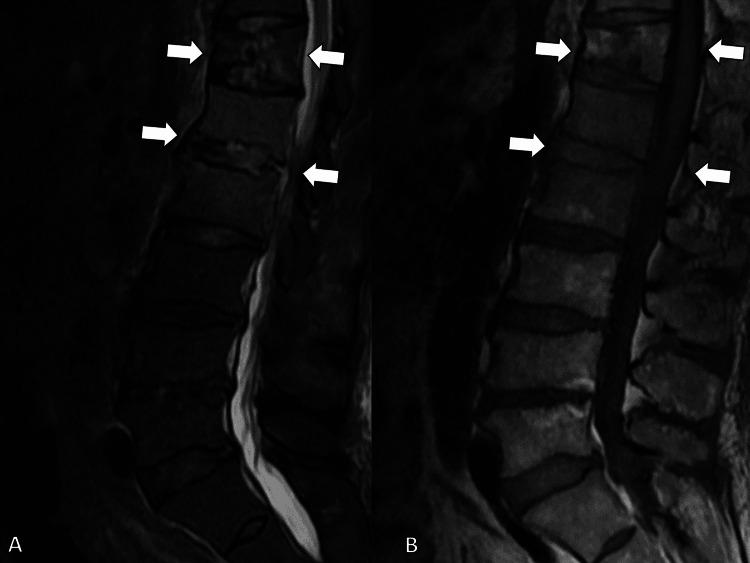

一名患有多种合并症的82岁男性因发热和活动能力下降前往一家乡村医院就诊,被诊断为高毒力肺炎克雷伯菌(HVKP)所致的肝脓肿。最初采用静脉抗生素治疗使影像学表现有所改善,但患者出现复发性菌血症、腰痛,最终发展为硬膜外脓肿、感染性心内膜炎和脑脓毒性栓子。尽管升级了抗生素治疗并给予支持治疗,但其病情仍恶化,由于严重脓毒症和心力衰竭,手术干预被认为不可行。他于住院第27天死亡。该病例凸显了HVKP感染的诊断和治疗挑战,尤其是在患有基础疾病的老年人中。即使早期治疗且原发性脓肿得到明显控制,HVKP仍可经血行播散,导致严重并发症。临床医生应高度怀疑其发生全身播散,并考虑延长治疗时间和加强监测,尤其是在老年或免疫功能低下的患者中。